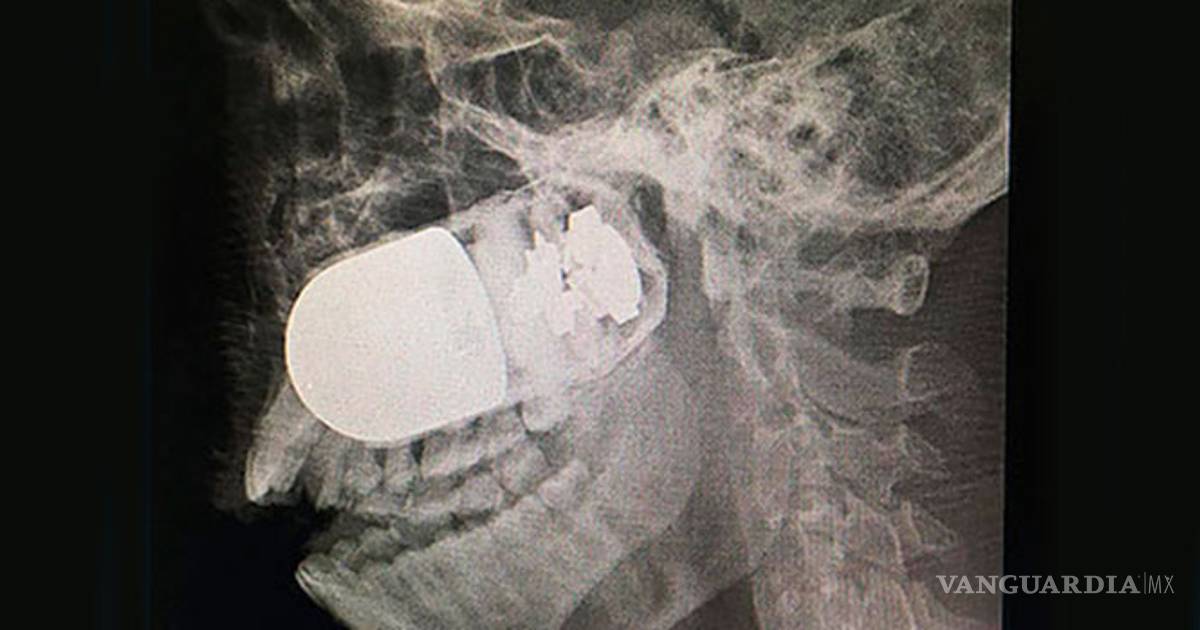

La cirugía para extraer una granada de asalto incrustada en el rostro de un soldado colombiano es un hecho excepcional y único en el mundo, porque estuvo en riesgo la vida del paciente y de todo el equipo médico del Hospital Militar Central, en esta capital.

El médico jefe de cirugías del Hospital Militar Central, William Sánchez, explicó a la prensa local que el soldado Leandro José Luna llegó el domingo pasado al centro hospitalario procedente del departamento de Arauca, en el suroccidente del país, por vía terrestre, ante la imposibilidad de trasladarlo en avión.

Explicó que el soldado no podía ser trasladado vía aérea por el riesgo que explotara la granada de asalto M40, que tenía incrustada en el rostro. Por esta razón fue movilizado en una ambulancia durante un recorrido de más de ocho horas.

El pasado fin de semana, el soldado estaba patrullando en las inmediaciones del río Tame, Arauca, cuando uno de sus compañeros activó en forma accidental un lanzagranadas MGL, y como consecuencia una granada se le incrustó en el rostro de Luna.

El militar “llegó en estado crítico al hospital y se tomó la decisión de atender con rapidez al paciente. El equipo quirúrgico tenía un riesgo muy elevado”, señaló Sánchez.

Insistió que este es un caso inusual, único a nivel mundial, porque se tuvo que montar todo el dispositivo médico para la cirugía en el estacionamiento a cielo abierto del Hospital Militar Central, con apoyo de expertos en explosivos para tener controlada la granada.

Fue una intervención de altísimo riesgo para el paciente y el equipo médico por el alto poder explosivo que tienen las granadas de asalto, que son utilizadas en la confrontación armada que vive este país desde hace 52 años de guerra.

Después de la exitosa intervención, el soldado se encuentra estable y en recuperación.